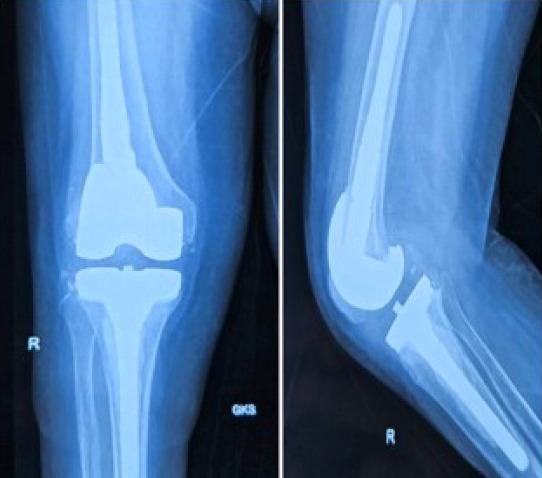

A. xylosoxidans is a pathogen capable of causing prosthetic joint infection even in immunocompetent patients. Thorough debridement and appropriate antibiotic treatment is essential for the success of revision surgery.

木糖氧化无色杆菌是一种即使在免疫功能正常的患者中也能引起人工关节感染的病原体。彻底清创和适当的抗生素治疗对于翻修手术的成功至关重要。